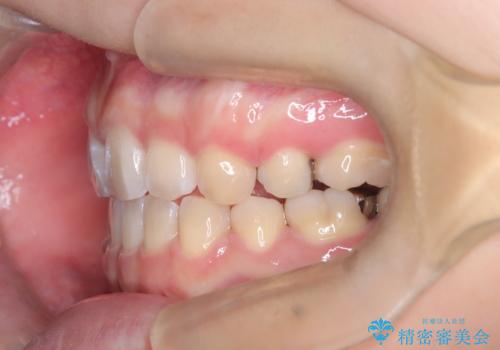

- 口元が出ている(突出している)ことを気にされて来院されました。精密な検査の結果、前歯を大きく後退させるスペースが必要と診断。患者様の**「前歯を下げたい」という強いご要望に応えるため、上下左右の第一小臼歯を抜歯し、そのスペースを利用して前歯を奥へ移動させる治療計画を立案しました。また、人目を気にせず治療できるよう、上顎に裏側矯正、下顎に表側矯正を組み合わせたハーフリンガル矯正**を提案しました。

今回の矯正治療では、前歯を大きく後退させるスペースを確保するため、計画通り上下左右の第一小臼歯を抜歯しました。装置には、上顎には目立たない裏側矯正(舌側矯正)を、下顎には透明な審美ブラケットを使用するハーフリンガル矯正を採用しました。抜歯によってできたスペースを最大限に活用し、前歯を効率よく後方へ移動。治療の結果、口元の突出感が大幅に解消され、Eライン(横顔の美しさの基準)も改善しました。人目を気にすることなく治療を完遂し、自信の持てる美しい横顔を獲得していただけました。